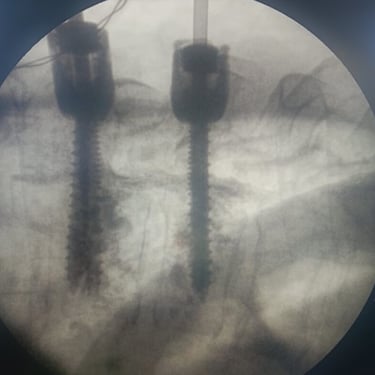

🧠 Fractura Vertebral Lumbar: Estabilización Segura con Fijación Transpedicular (FTP).

La fractura vertebral lumbar genera inestabilidad y dolor severo. La artrodesis con fijación transpedicular es una técnica quirúrgica eficaz que estabiliza la columna, previene desplazamientos vertebrales y mejora la recuperación funcional del paciente.